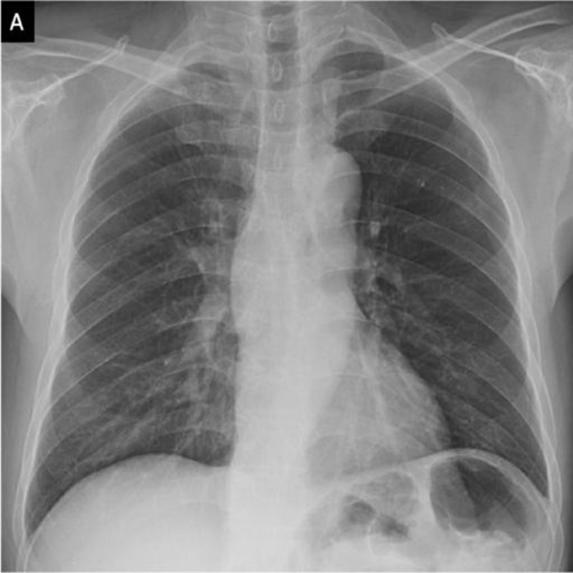

In this project ,we aim to propose a fully-automated method to detect/screen COVID-19 from the patient’s chest X-ray scanned images with out needing a clinical technician.

I've teamed up with AI enthusiasts and got inspired from the several news articles to create a end to end web application using Deep learning.We have collected datasets from Mendeley and Qatar University which were posted on kaggle website.We augumented the images and trained the model to detect the hidden patterns in the images and using "Transfer Learning" approach we have used the model to deploy it on cloud platform and hooked it via flask server.

The main challenge was the dataset of X-ray images from medical institutions. Unitl now the Covid19 dataset is not shared to public by most of the countries which could have paved the way for more developers or scientists to find out a better way to deal with this pandemic